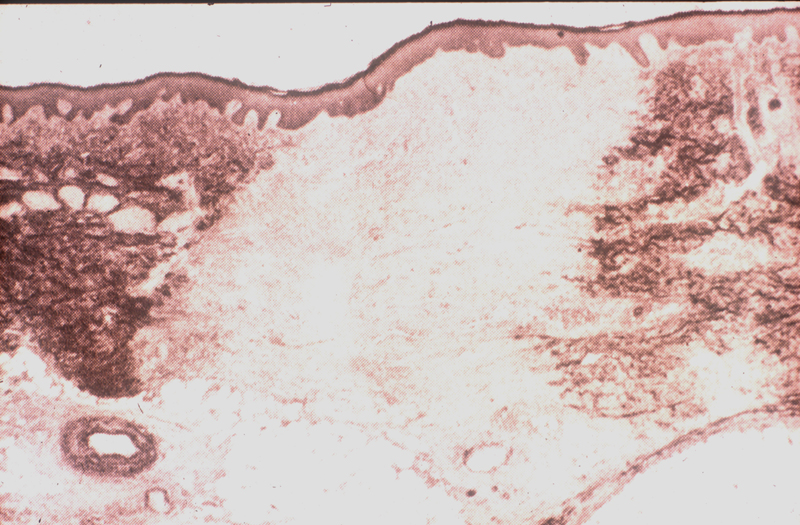

Imágenes histológicas

cicatriz01p.JPG (321749 bytes) cicatriz02p.JPG (492337 bytes) cicatriz03p.JPG (236643 bytes)